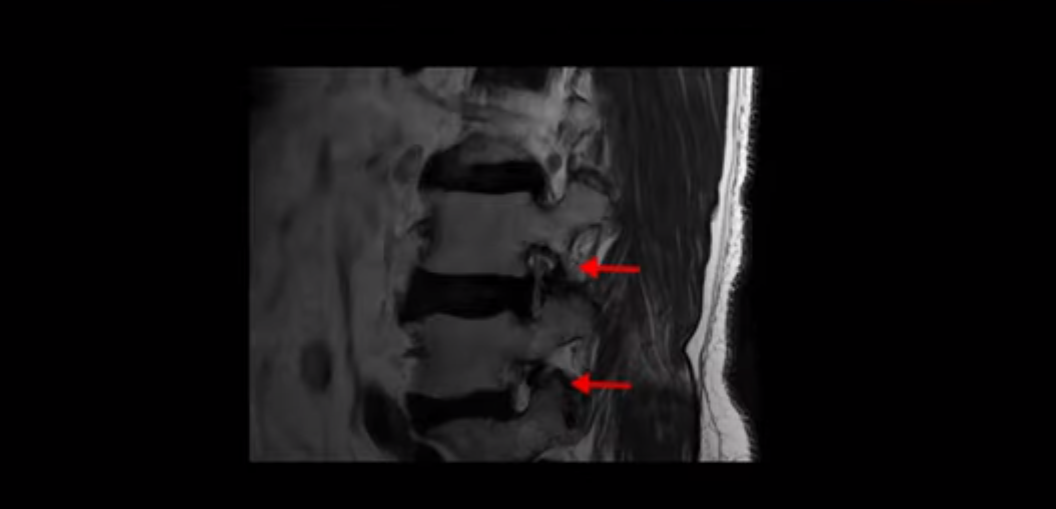

이 환자분은 고관절 쪽이 10년이 넘게 아팠고, 5년 전에는 갑자기 허벅지와 다리가 아파 못 걷게 돼서 허리 수술을 받습니다. 그리고 3년 후에 다시 재발합니다. 고관절 통증은 허리 수술 이후에도 좋아지지 않고 계속 아팠습니다. 수술하고 재발한 이후로 원래부터 아프던 고관절은 물론, 양쪽 엉덩이와 사타구니 및 허벅지가 다 아파서 잘 걷지도 못하고 또 앉거나 누워도 아파서 뒤척거리기도 힘듭니다. 이분 MRI를 보면 여러 마디가 다 안 좋습니다.

2번 3번은 디스크가 심하게 터져있고 협착까지 있습니다.

4번 5번에는 왼쪽으로 이전에 수술한 자국이 보이는데

수술한 부위에 상처 조직이 생겨 유착된 부위가 보입니다. 왼쪽, 오른쪽 신경 가지가 빠져나가는 추간공을 보면 오른쪽도 여러 마디가 좁아져 있고

왼쪽도 여러 마디가 좁아져 있습니다.

이렇게 허리 여러 마디와 신경 나가는 구멍 오른쪽, 왼쪽이 다 안 좋으니까 양쪽 엉덩이와 다리가 다 아픈 겁니다.